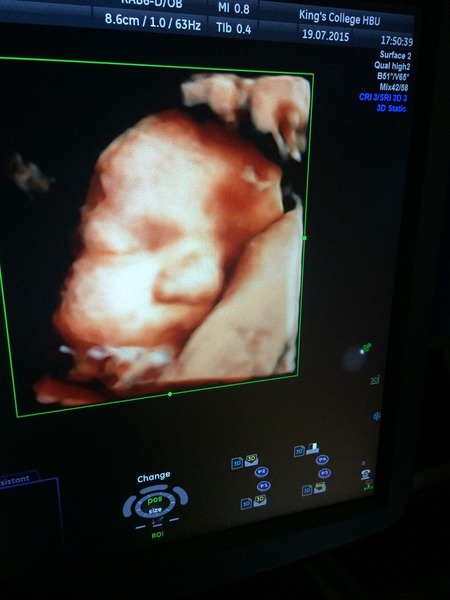

I don't know where today has gone! Cinema was good, had a lovely alfresco lunch in the garden with DH (we're friends again now lol). We finally took the pram and all the bits and pieces out of their boxes. Now I thought we'd picked a light one, honestly I don't know if I'm just a weed but I swear I need to get some muscles pronto lol. DH and I were shattered and the baby isn't even in it yet haha. Then before I knew it was time to head back to the hospital for the 3D scan! It was so lovely!! I'm really pleased we did it actually, she was being naughty with her arm over her face and then turned towards my back but we managed to move her. She looks so peaceful and cute, she was sucking her fingers which DH apparently used to do as a baby. I'll try and put a pic up but I'm on my phone...

And here she is!! :) little piglet! x

Oh Fanby that's so clear - and on colour too! Amazing!!!! Can't you even believe that's inside you?! Grin

Not at all!! It's completely surreal! We took that photo from the monitor but they also printed some black and white ones for us which was lovely. My mum thinks she looks just like I did. I literally am so excited to meet her now!! Need those cuddles in my life!! xx

How cute is she fanby! I bet you can't wait to meet her now. I'm quite jealous of all of you who've got to see their babies again. We've not seen him since 20 weeks. I wish we'd booked a 3/4d scan now. Hopefully he won't keep us waiting too long.